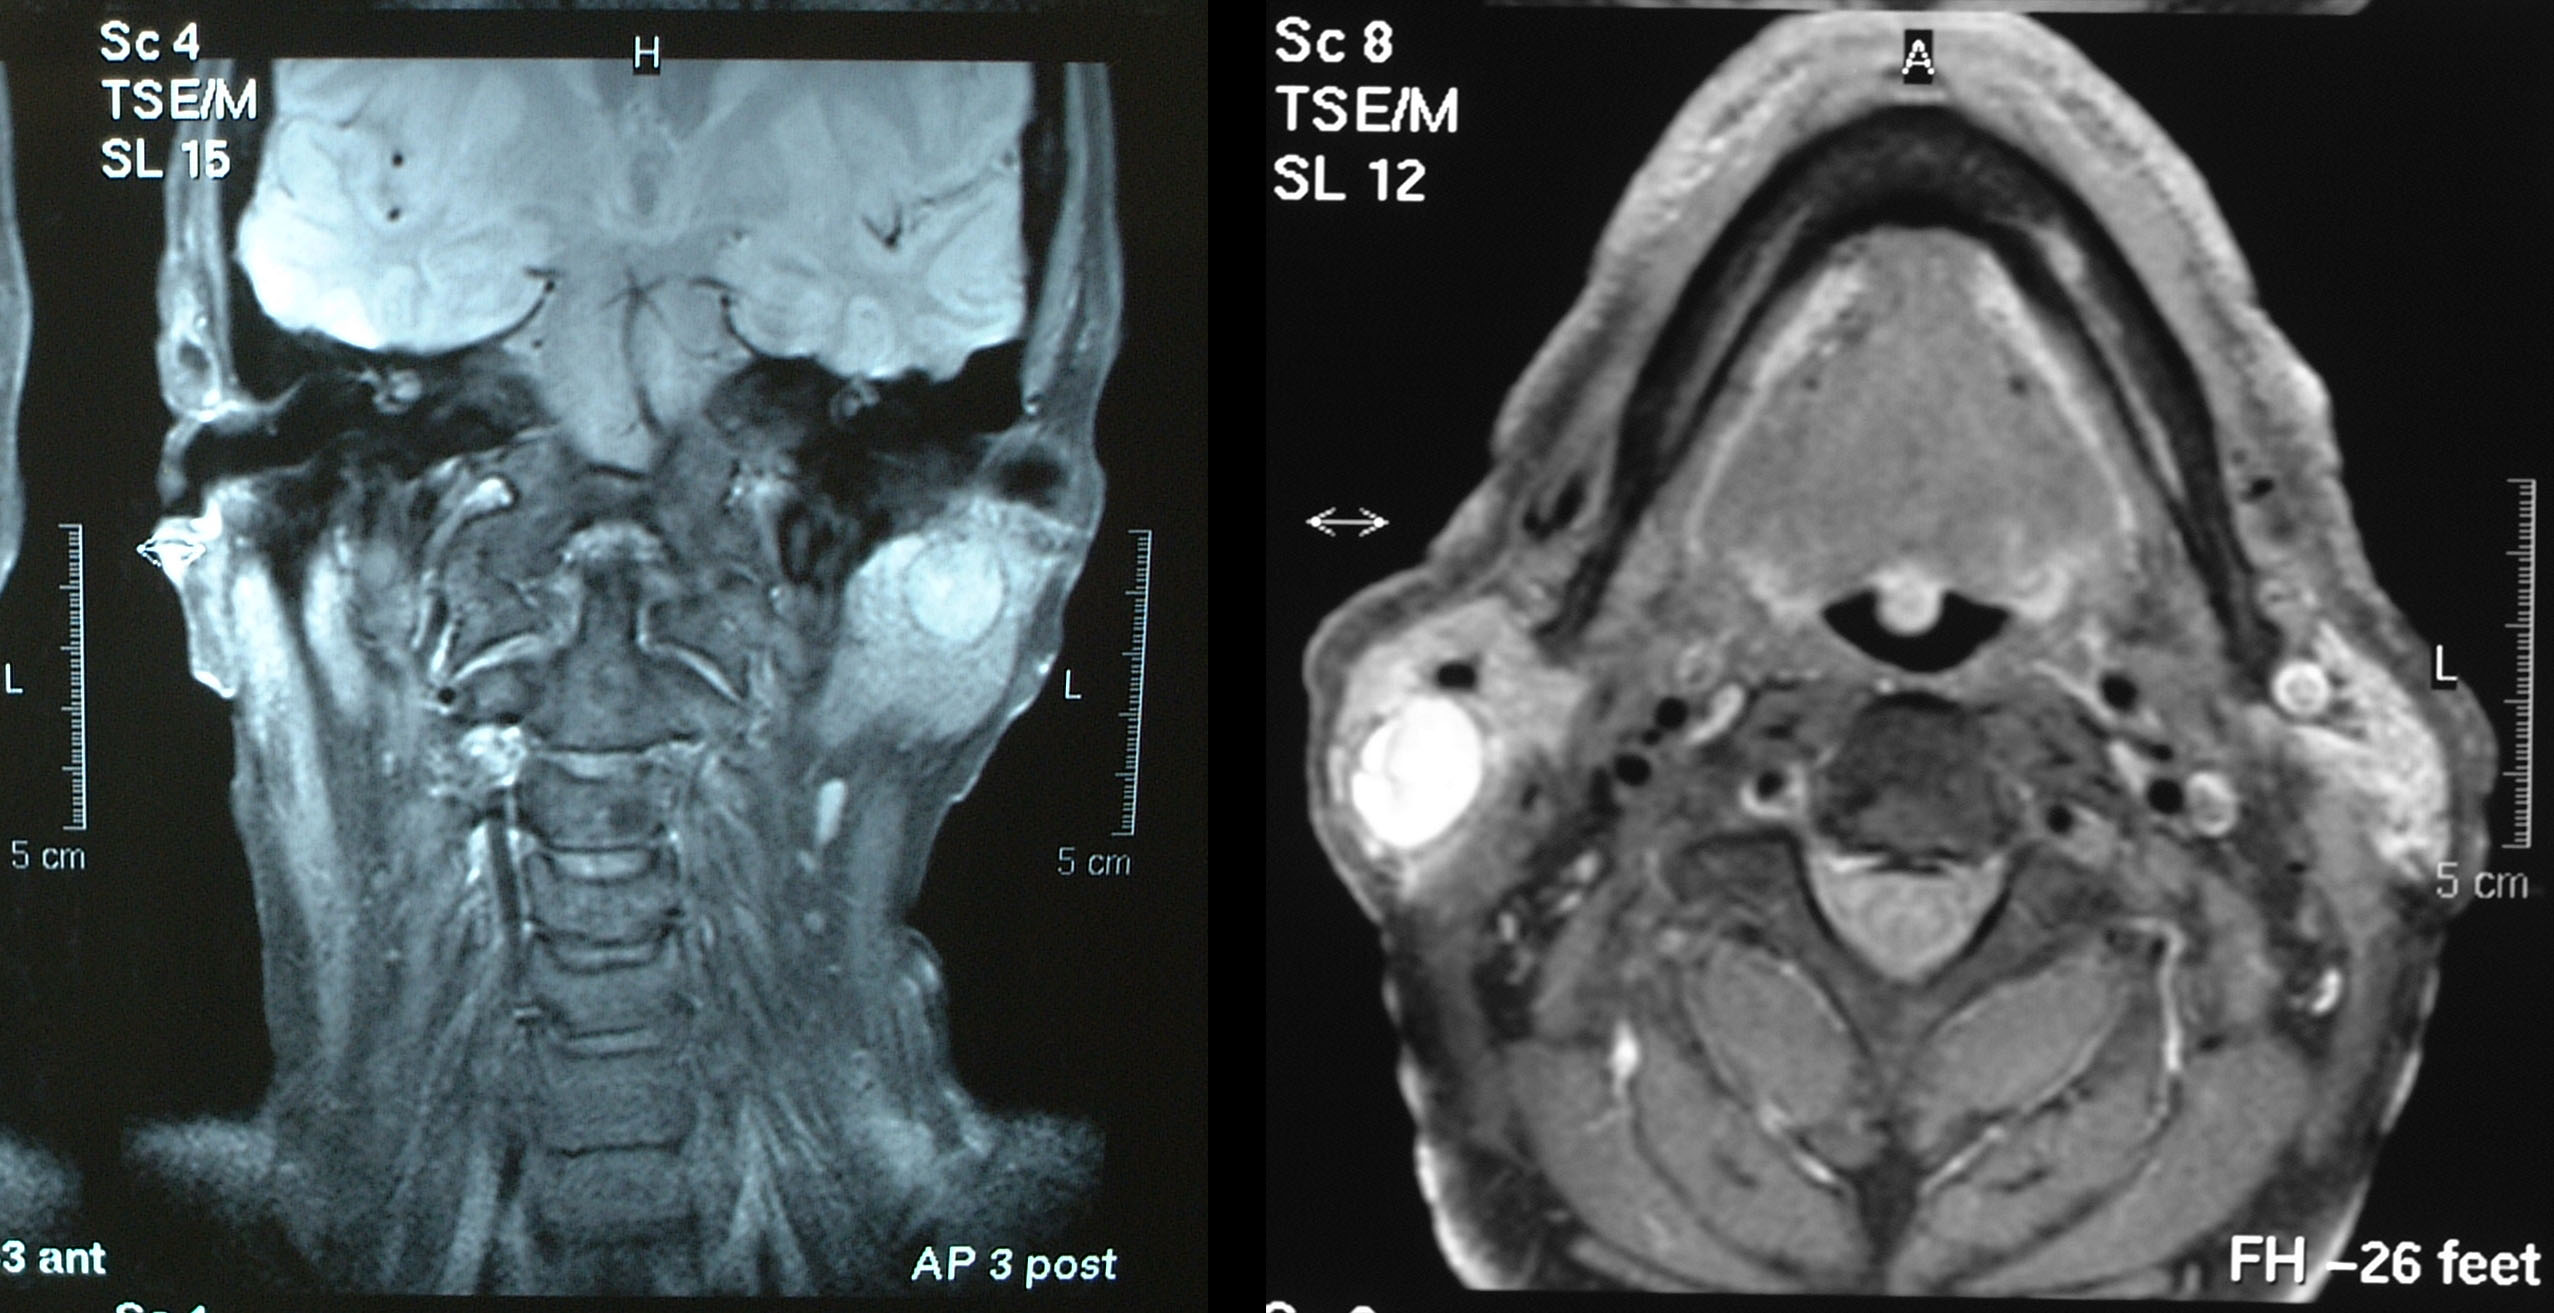

The parotid gland consists almost entirely of serous acini (cells that produce serous (watery) fluid; see below about physiology). The gland lies in the retromandibular fossa (near the angle of the mandible and in front of the ear) and has three surfaces. Its lateral surface is located subcutaneously and is enveloped in a tight fascia (connective tissue). This fascia is related to the subcutaneous musculoaponeurotic system (SMAS layer: a fairly inelastic layer of fibres and muscles in the deep skin layers of face and neck), with the greater auricular nerve branching anteriorally (in the front) into the skin and to the posterior (to the back) to the lobe of the ear. Its anterior surface wraps around the posterior border of the ramus of the mandible (the part of the mandible rising from the mandibular body, posterior to the molar teeth) and abuts the masseter and medial pterygoid muscles (cheek muscles). The deep surface of the parotid gland is complex and is related to the mastoid process (a space at the base of the skull, behind the ear), the posterior belly of the digastric muscle (small muscle under the jaw), the styloid process (small bone beneath the ear) and its associated muscles and ligaments, and the external carotid artery. Figure 1 shows MRI views of the parotid glands from two different angles.

Figure 1: Two MRI views of the parotid glands. Left: coronal (vertical) view, right: axial (horizontal) view.